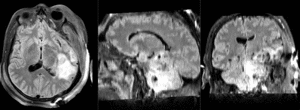

RegLib C38 Thumb1.png lleft RegLib C38 Thumb2.png RegLib C38 Thumb3.png RegLib C38 Thumb4.png RegLib C38 Thumb5.png RegLib C38 Thumb6.png RegLib C38 Thumb7.png RegLib C38 Thumb8.png

T1pre FLAIR T1post coronal T2 SWI EP50 EP75 EP100

This is an example of a multi-contrast dataset acquired for traumatic brain injury (TBI). We have many scans we seek to align to a common reference. Since all scans are acquired in short succession, they have only little initial misalignment, but they may differ significantly in contrast and field of view.

Approach: we register all the scans within each exam to the T1. Because of the strong differences in field of view (FOV), we limit registration degree of freedom to 6 DOF (rigid transformation only).